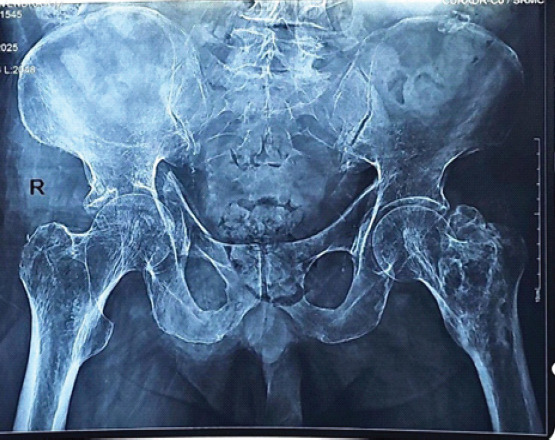

Case report: A 63-year-old male presented with right hip pain and inability to bear weight after a standing-height fall. Imaging revealed a comminuted right acetabular fracture with superomedial dome impaction, quadrilateral plate involvement, and central subluxation. The patient underwent open reduction and internal fixation through a modified Stoppa approach using a suprapectineal plate. Postoperatively, an accelerated rehabilitation protocol was implemented, progressing to full weight-bearing by 6 weeks with radiographic evidence of union.